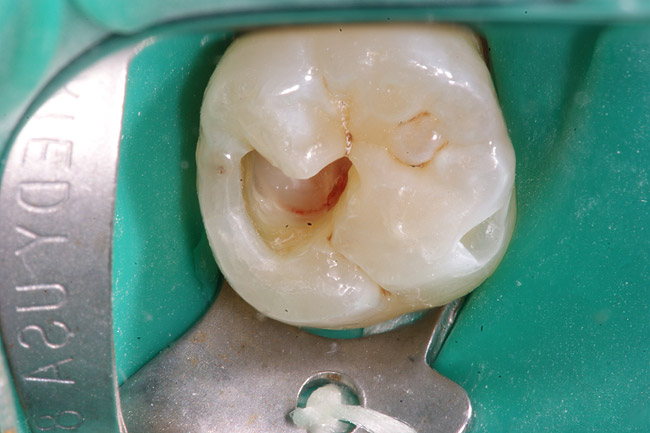

Figure 8D Removal of caries reveals necrotic pulp (no frank bleeding when the pulp was exposed.

Figure 8D